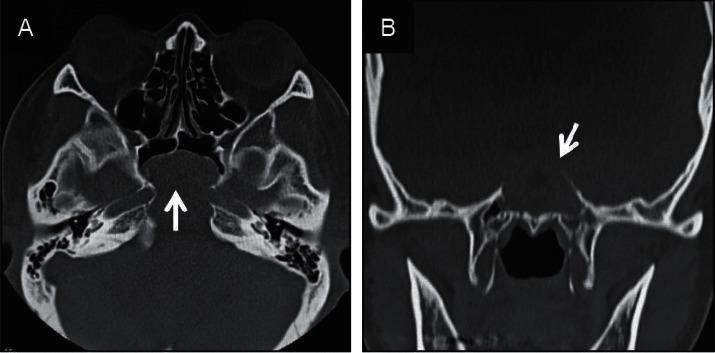

Primary solitary sphenoid sinus mucocele is rare, generally presenting with headaches or eye symptoms at the anatomical site. We report the case of a 39-year-old woman incidentally diagnosed with sphenoid sinus mucocele during a complete medical checkup. Imaging revealed that the cystic wall had developed from the rear sphenoid sinus and had spread expansively to diminish the clivus; however, no symptoms were reported, and the patient was managed with close observation. During the follow-up period, diplopia developed suddenly due to isolated left-sided abducens nerve paralysis. An endoscopic endonasal approach was used to open the frontal cystic wall, and fascia lata and fat were used for cranial base reinforcement to avoid future cerebrospinal fluid leakage, resulting in improvement during the early stages of follow-up. Treatment options for sphenoid sinus mucoceles include close observation or surgery. In our case, we chose surgery because of an acute symptomatic manifestation during observation.

原发性孤立性蝶窦黏液囊肿罕见,通常在解剖部位出现头痛或眼部症状。我们报告了一例39岁女性在全面体检时偶然诊断为蝶窦黏液囊肿的病例。影像学检查显示,囊肿壁由后蝶窦发展而来,并呈膨胀性扩展,致使斜坡骨质吸收;然而,患者并无症状报告,遂对其进行密切观察。在随访期间,患者突然因孤立性左侧展神经麻痹出现复视。采用鼻内镜经鼻入路打开额部囊肿壁,并使用阔筋膜和脂肪进行颅底加固,以避免未来脑脊液漏,在随访早期病情有所改善。蝶窦黏液囊肿的治疗选择包括密切观察或手术。在我们的病例中,由于观察期间出现急性症状表现,我们选择了手术治疗。